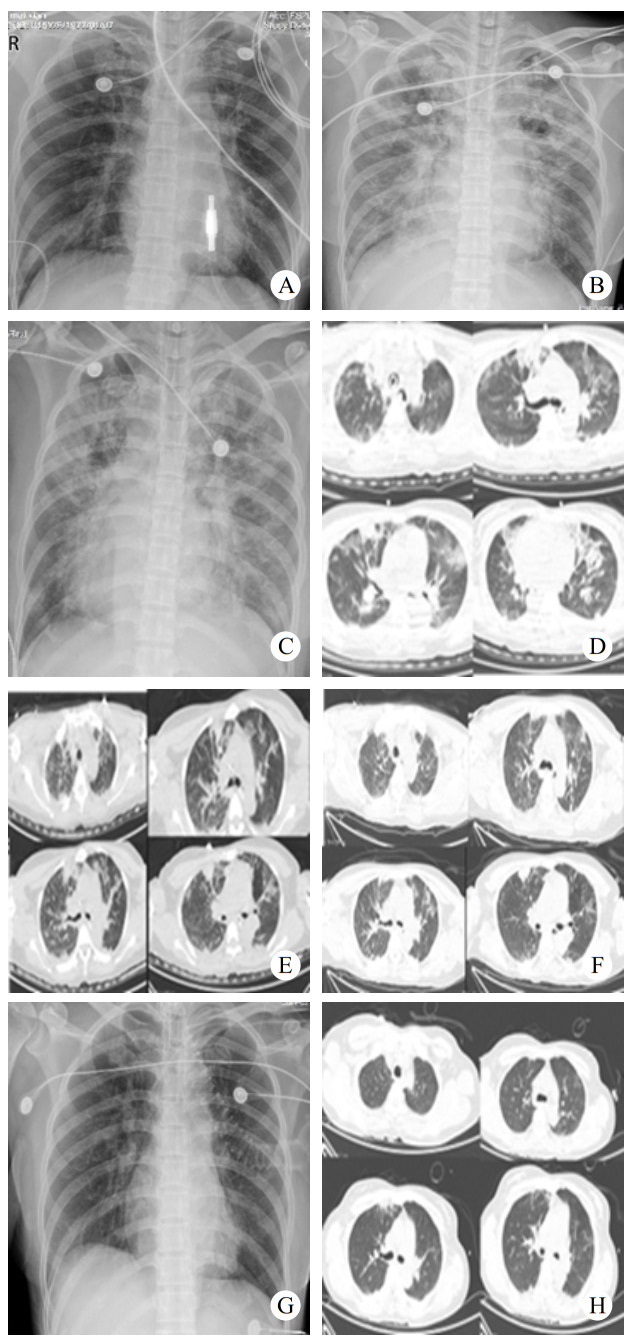

2 结果入院时实验室查急诊血清胆碱酯酶(cholinesterase, ChE):小于196 U/L。血常规:白细胞(white blood cell, WBC)9.24×109/L,中性粒细胞百分比(neutrophil, NEUT%)88.3%,PLT 230×109 /L,红细胞(red blood cell, RBC) 4.08×109/L血红蛋白(hemoglobin, Hb)128 g/L。动脉血气分析:酸碱度(potential of hydrogen, pH)7.247,二氧化碳分压(partial pressure of carbon dioxide, PCO2)30.2 mmHg,氧分压(partial pressure of oxygen, PaO2)93.8 mmHg(呼吸机辅助通气下吸氧浓度为50%),氧合指数284.3%,血钠(Na+) 141.1 mmol/L,血钾(K+) 3.25 mmol/L,乳酸(lactic acid, Lac)8.35 mmol/L,血糖16.05 mmol/L,碳酸氢根12.8 mmol/L,碱剩余-13.2 mmol/L。床旁快速心肌酶:心脏特异性肌钙蛋白Ⅰ(cardiac troponin, cTnⅠ)0.17 ng/mL,肌红蛋白(myoglobin, Myo)123.6 ng/mL,肌酸激酶同工酶(creatine kinase, myocardial-type, CK-MB)17.83 ng/mL。床旁NT-proBNP: 106 ng/L,肝功能:天门冬氨酸氨基转移酶(aspartate aminotransferase, AST)162 U/L,丙氨酸氨基转移酶(alanine aminotransferase, ALT)86 U/L,肌酸激酶196 U/L,乳酸脱氢酶(lactate dehydrogenase, LDH)302 U/L。肾功能:肌酐(creatinine, CREA)104 μmol/L,尿素氮4.84 mmol/L。凝血常规:PT 12.9 s,APTT 34.7 s。新冠病毒抗体阴性。急性感染三项:白介素6 1 148.0 pg/mL,降钙素原(procalcitonin, PCT)0.688 ng/mL,超敏C反应蛋白0.78 mg/L。后期上述指标变化见图 1。床旁胸片显示,(1)双肺纹理增多、增粗、模糊,双肺感染可能;(2)左侧胸腔少量积液可能。见图 2。住院期间讨论CT示:硬膜下积液,见图 3。

| 注:A: 2022-07-16床旁胸片示双肺纹理增多;B:2022-07-18床旁胸片示双肺感染,间质性肺水肿可能;C:2022-07-19床旁胸片示双肺感染;D:2022-07-21胸部CT示①双肺感染、间质性肺水肿可能;②右肺上中叶及左肺上叶结节状模糊影,炎性可能,请复查;③双侧胸腔积液,双肺下叶部分不张;E:2022-07-24胸部CT示对比2022-07-21①双肺散多发感染,双肺散在肺组织不张、部分实变,大致同前;②间质性肺水肿,较前加重。③双侧胸腔少量积液,大致同前;F:2022-07-26胸部CT示对比2022-07-24 CT,①双肺散多发感染,双肺散在肺组织不张、部分实变,同前;②间质性肺水肿,同前;③右肺上叶尖段磨玻璃结节,建议复查;④双肺上叶、右肺下叶多发实性结节,考虑炎性,建议复查;⑤双侧胸腔少量积液,较前减少;G:2022-07-29床旁胸片示双肺散在多发感染;H:2022-08-01对比2022-07-26 CT:①双肺散多发感染,双肺散在肺组织不张、部分实变,较前稍减轻;②间质性肺水肿较前减轻 图 2 患者住院期间肺部主要影像学变化 |